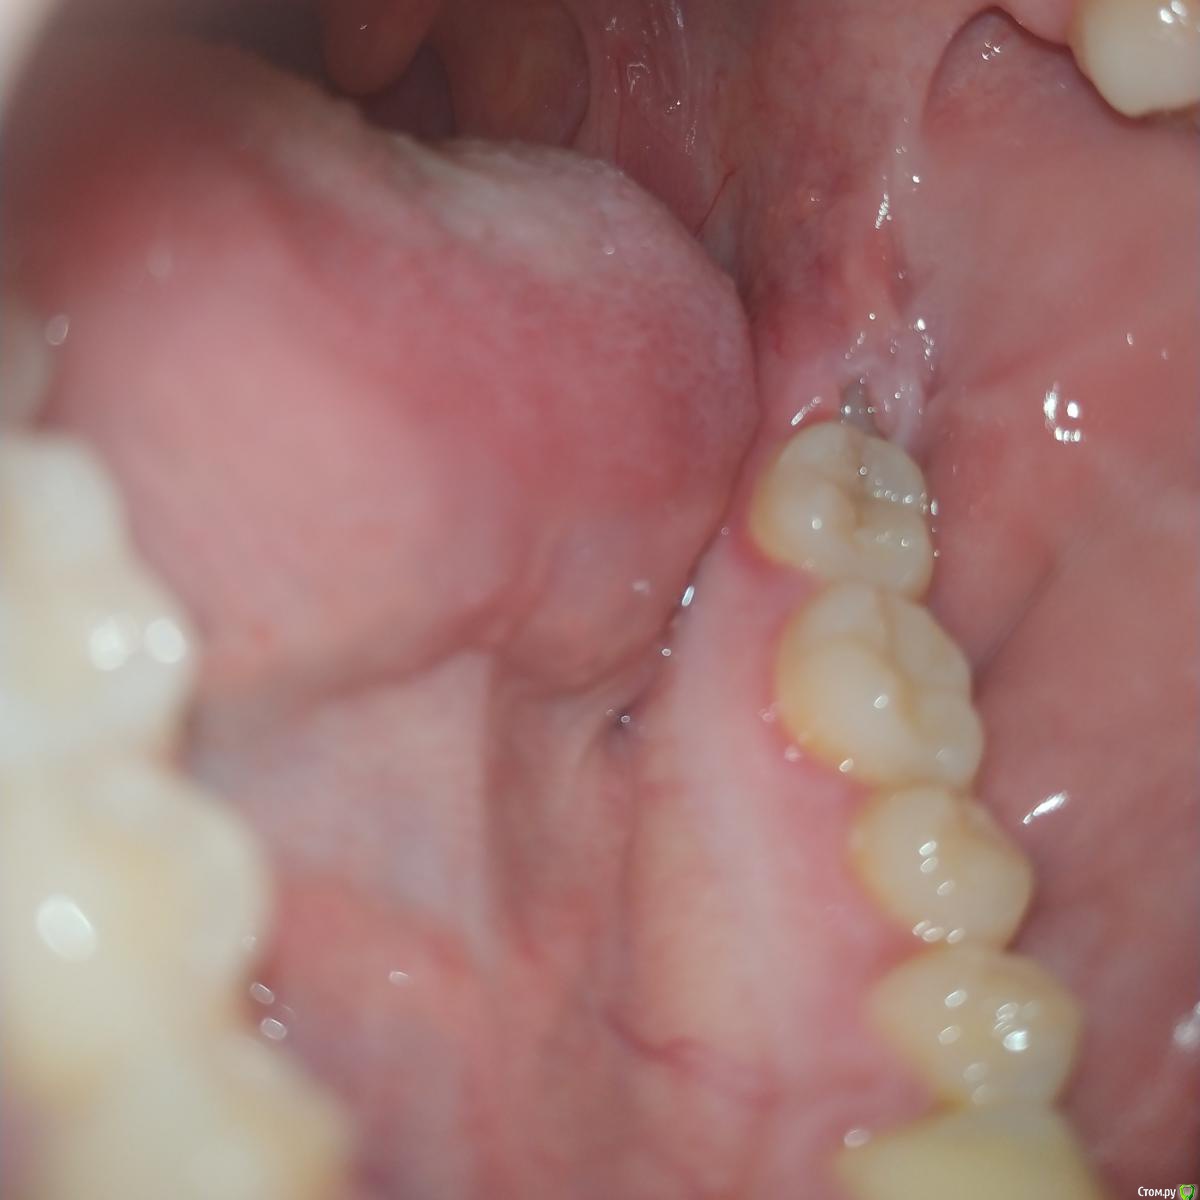

Daria___ Опубликовано 8 декабря, 2019 Поделиться Опубликовано 8 декабря, 2019 (изменено) День добрый. На данный момент нахожусь в другой стране и столкнулась с проблемой зуба мудрости- зуб с левой стороны челюсти не до конца прорезан и находится под капюшоном. Далее всё как по книжке- ноющая боль, небольшое воспаление,потом нагноение под капюшоном. Температуры и отёка пока нет. Сходив к местному врачу получила рекомендацию на удаление зуба. Причем сразу с зубом- антагонистом.Отправила рентген своему семейному врачу: он сказал что места под зуб маловато, но, в целом зуб выглядит пока не плохо. получила рекомендацию полоскать рот мирамистином и раствором соли и ждать как зуб покажет себя в прогрессеЗуб болит уже неделю, полоскания вомпроизвожу 2-3 раза в день третий день. Нагноения вчера после полоскания стало даже немного больше, на что мой отец высказал мнение что это не показатель распространения инфекции, а соль вытягивает гной на поверхность. В общем, у меня тут уже целый консилиум, а что делать так и не решилась. Ибо всё же другая страна, на операцию идти немного боязно ввиду своей правовой незащищенности, хотя многие люди этого врача рекомендовали, в том числе по операции по удалению сложного зуба мудрости. Надеюсь на дополнительные профессиональные отзывы о данной ситуации. Удалять зуб(ы)? Иссекать десну? Продолжать полоскать и ждать? Изменено 8 декабря, 2019 пользователем Daria___ Ссылка на комментарий